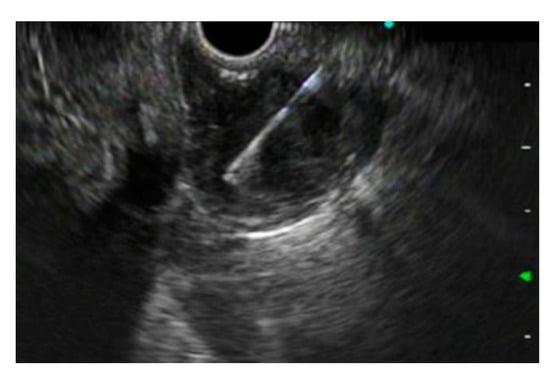

7. The Use of Through-the-Needle Imaging